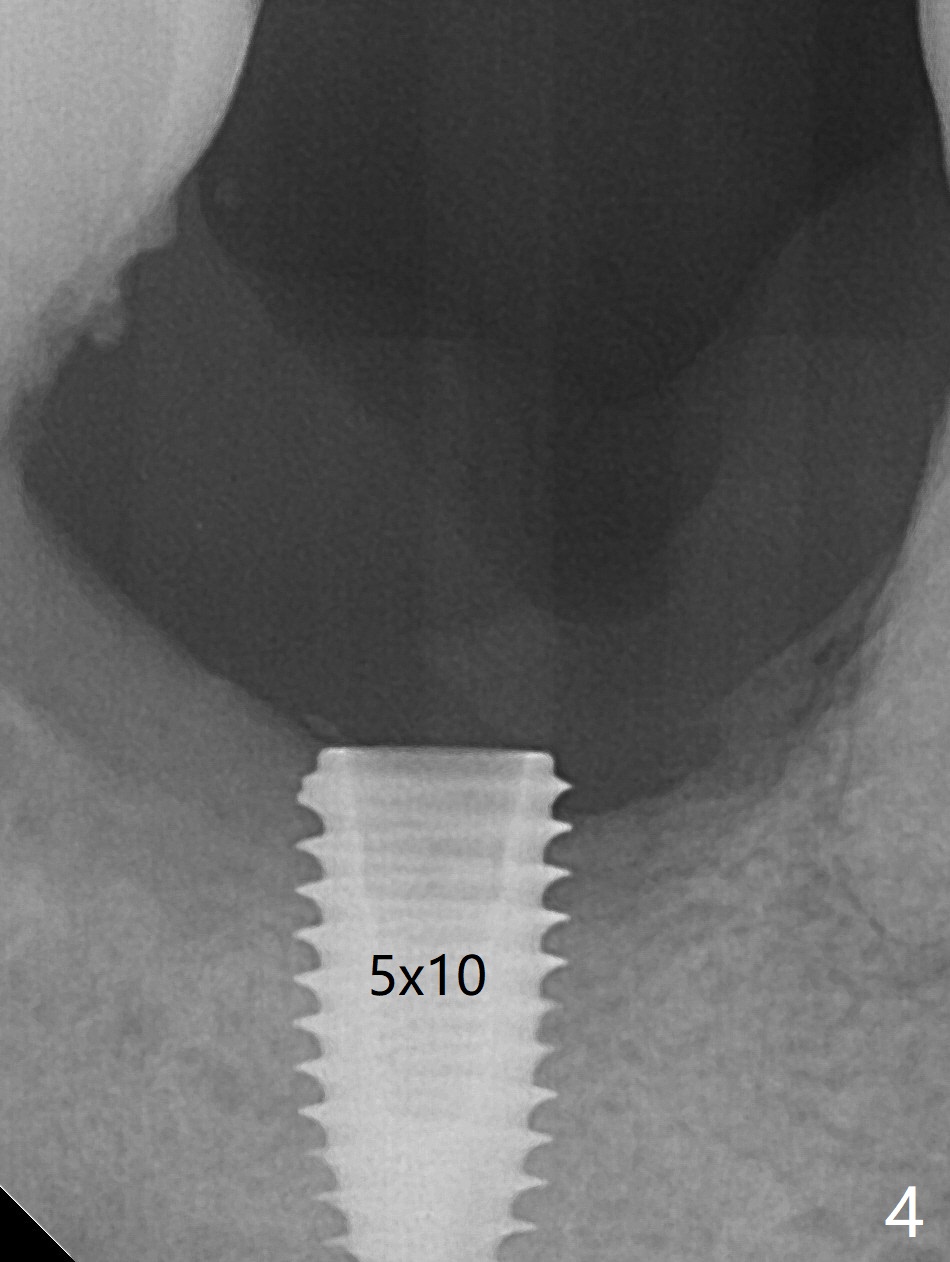

The affected tooth (#31, Fig.1) has severe buccal gingival recession with mobility III. After extraction and removal of granulation tissue, osteotomy is initiated in the middle of the fused socket using IS drills with 4 mm stopper (Fig.2,3). Following sequential osteotomy until 4 mm drill, a 4.5x10 mm IS dummy implant does not achieve primary stability, whereas 5x10 mm one does (Fig.4,5). Due to limited bone height confirmed intraoperatively, a shorter UF implant is placed with insertion torque 30 Ncm (Fig.6,7) with ~ 4.5 mm implant threads exposed coronally. After placing a 6.5x5(5) mm abutment, Vanilla Graft (*) and PRF membrane and collagen plug, an immediate provisional is fabricated to close the remaining socket. The tooth #32 is kept initially to increase the stability of the provisional and removed 8 day postop because of discomfort. A 5.5(2.5) mm mill abutment is changed to 3 months postop. The implant seems ready for impression 6 months postop (Fig.8). The bone graft remains around the apical portion of the mill abutment with apparently new bone formation around the coronal portion of the implant10 months postop (Fig.9); porcelain (*) has been added to close the mesial gingival embrasure and proximal contact gap. Due to unfavorable crown/implant ratio and poor trajectory, the crown/abutment becomes loose once post 1st cementation. Guided surgery would avoid the trajectory isssue.